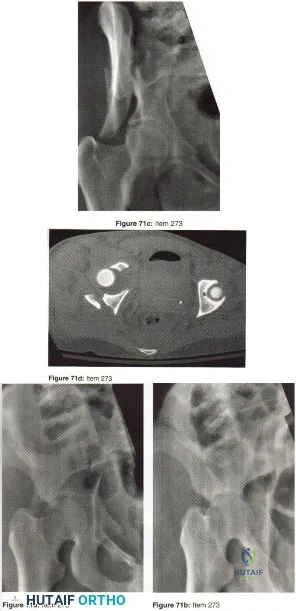

- Sacral fracture lateral to the foramina

- Sacral fracture medial to the foramina

- Sacroiliac fracture-dislocation

- Sacroiliac dislocation

- Iliac wing fracture